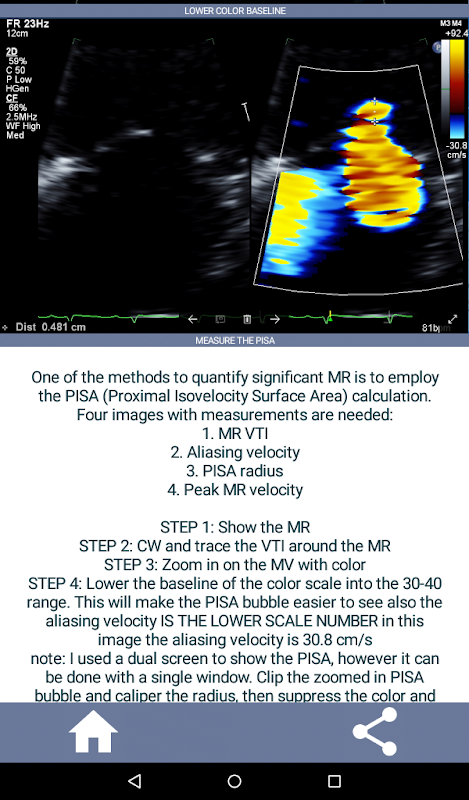

Vídeos y capturas de pantalla